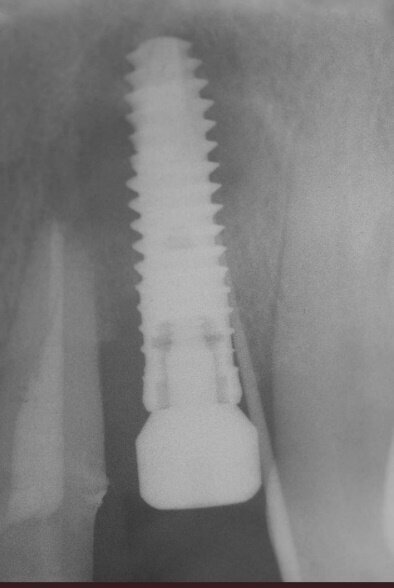

La fase chirurgica viene pianificata con la preparazione iniziale (igiene orale, controllo emato-chimico delle condizioni della paziente, prescrizione della profilassi/terapia antibiotica19-20 e della sospensione del fumo). Il 23 giugno 2011, vengono estratti i due incisivi laterali (Figg. 13, 14) e inseriti contestualmente due impianti Xive (Dentsply) di diametro 3,8 mm e lunghezza 15 mm (Figg. 15, 16), dimensioni ottimali per la successiva protesi (ponte di 4 elementi da 1.2 a 2.2 con 1.1 e 2.1, elementi “intermedi”).

Vengono inserite due viti di guarigione e riposizionato il provvisorio, debitamente adattato in corrispondenza dei due incisivi laterali. Alla seduta di controllo a una settimana dall’intervento implantare, la paziente confida, alle assistenti dello studio, di non aver assunto gli antibiotici prescritti né prima né dopo l’inserimento degli impianti e tantomeno di essersi astenuta o limitata dal fumo di sigarette! Alla seconda visita di controllo, dopo 30 giorni, la stessa presenta un pessimo stato di igiene orale e due ascessi vestibolarmente ai due impianti (1.2 e 2.2) (Figg. 17, 18).

L’odontoiatra, informata la paziente dell’accaduto la rende partecipe della necessità di rimuovere i due impianti21 e, preso atto della sua scarsa collaborazione, rinvia la rivalutazione dei siti implantari dopo circa 2 mesi. La paziente ammette le proprie responsabilità per non aver rispettato le prescrizioni del dentista.